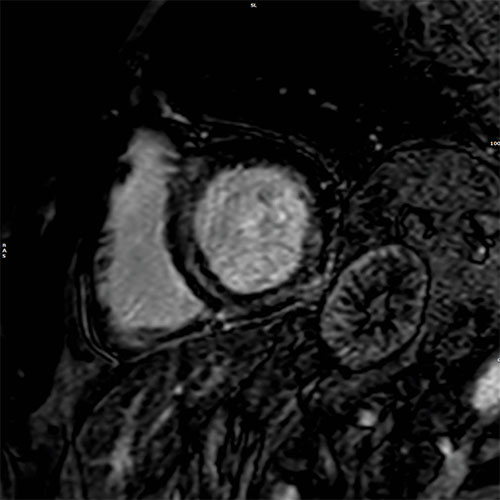

Cardiomyopathy

Cardiac MR images of a patient with non-ischemic cardiomyopathy showing delayed enhancement and severe mitral regurgitation.

PSIR - 4 chamber view

PSIR – short axis view

BTFE - 4 chamber view

BTFE 4 chamber view

EPI cine - 4 chamber view